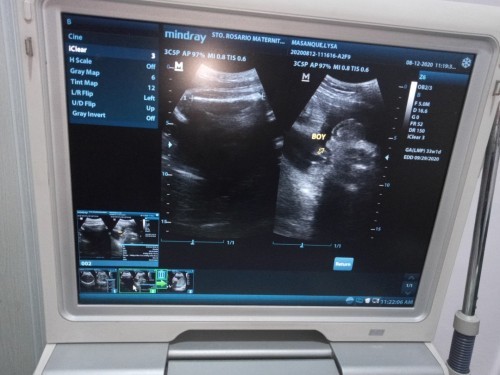

33 weeks pregnant

Hello mga mommy. Its my 33 Weeks Edd ko is Sept 29.Sabi ng OB ko 3kg na si baby.Normal lang po ba yun? Going to 8months palang kme ni baby. Pinag da diet na ako ng OB ko. Salamat po sa pagpasagot mga mommy